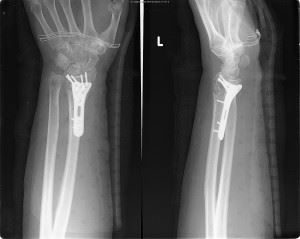

Normale linker pols

Gebroken linker pols

Voor de behandeling van instabiele, verplaatste fracturen maken de handchirurgen sinds jaren gebruik van een volaire plaat. Deze plaat volgt de anatomische vorm van de radius indien ze aan de onderzijde van de onderarm wordt geplaatst. Er zijn verschillende types. De keuze is afhankelijk van de fractuur. De handchirurgen kozen voor deze plaat omdat ze gebruik maakt van het principe hoekstabiliteit. Er zit namelijk in de schroefkop ook een schroefdraad. Door deze extra schroefdraad zit de schroef verankert in de plaat en wordt het risico op uitscheuren van de schroef uit het bot sterk beperkt. Het grote voordeel van deze volaire plaat is de vroege mobilisatie. Geleidelijk aan bewegen van de hand is al mogelijk vanaf 10 dagen na de operatie.